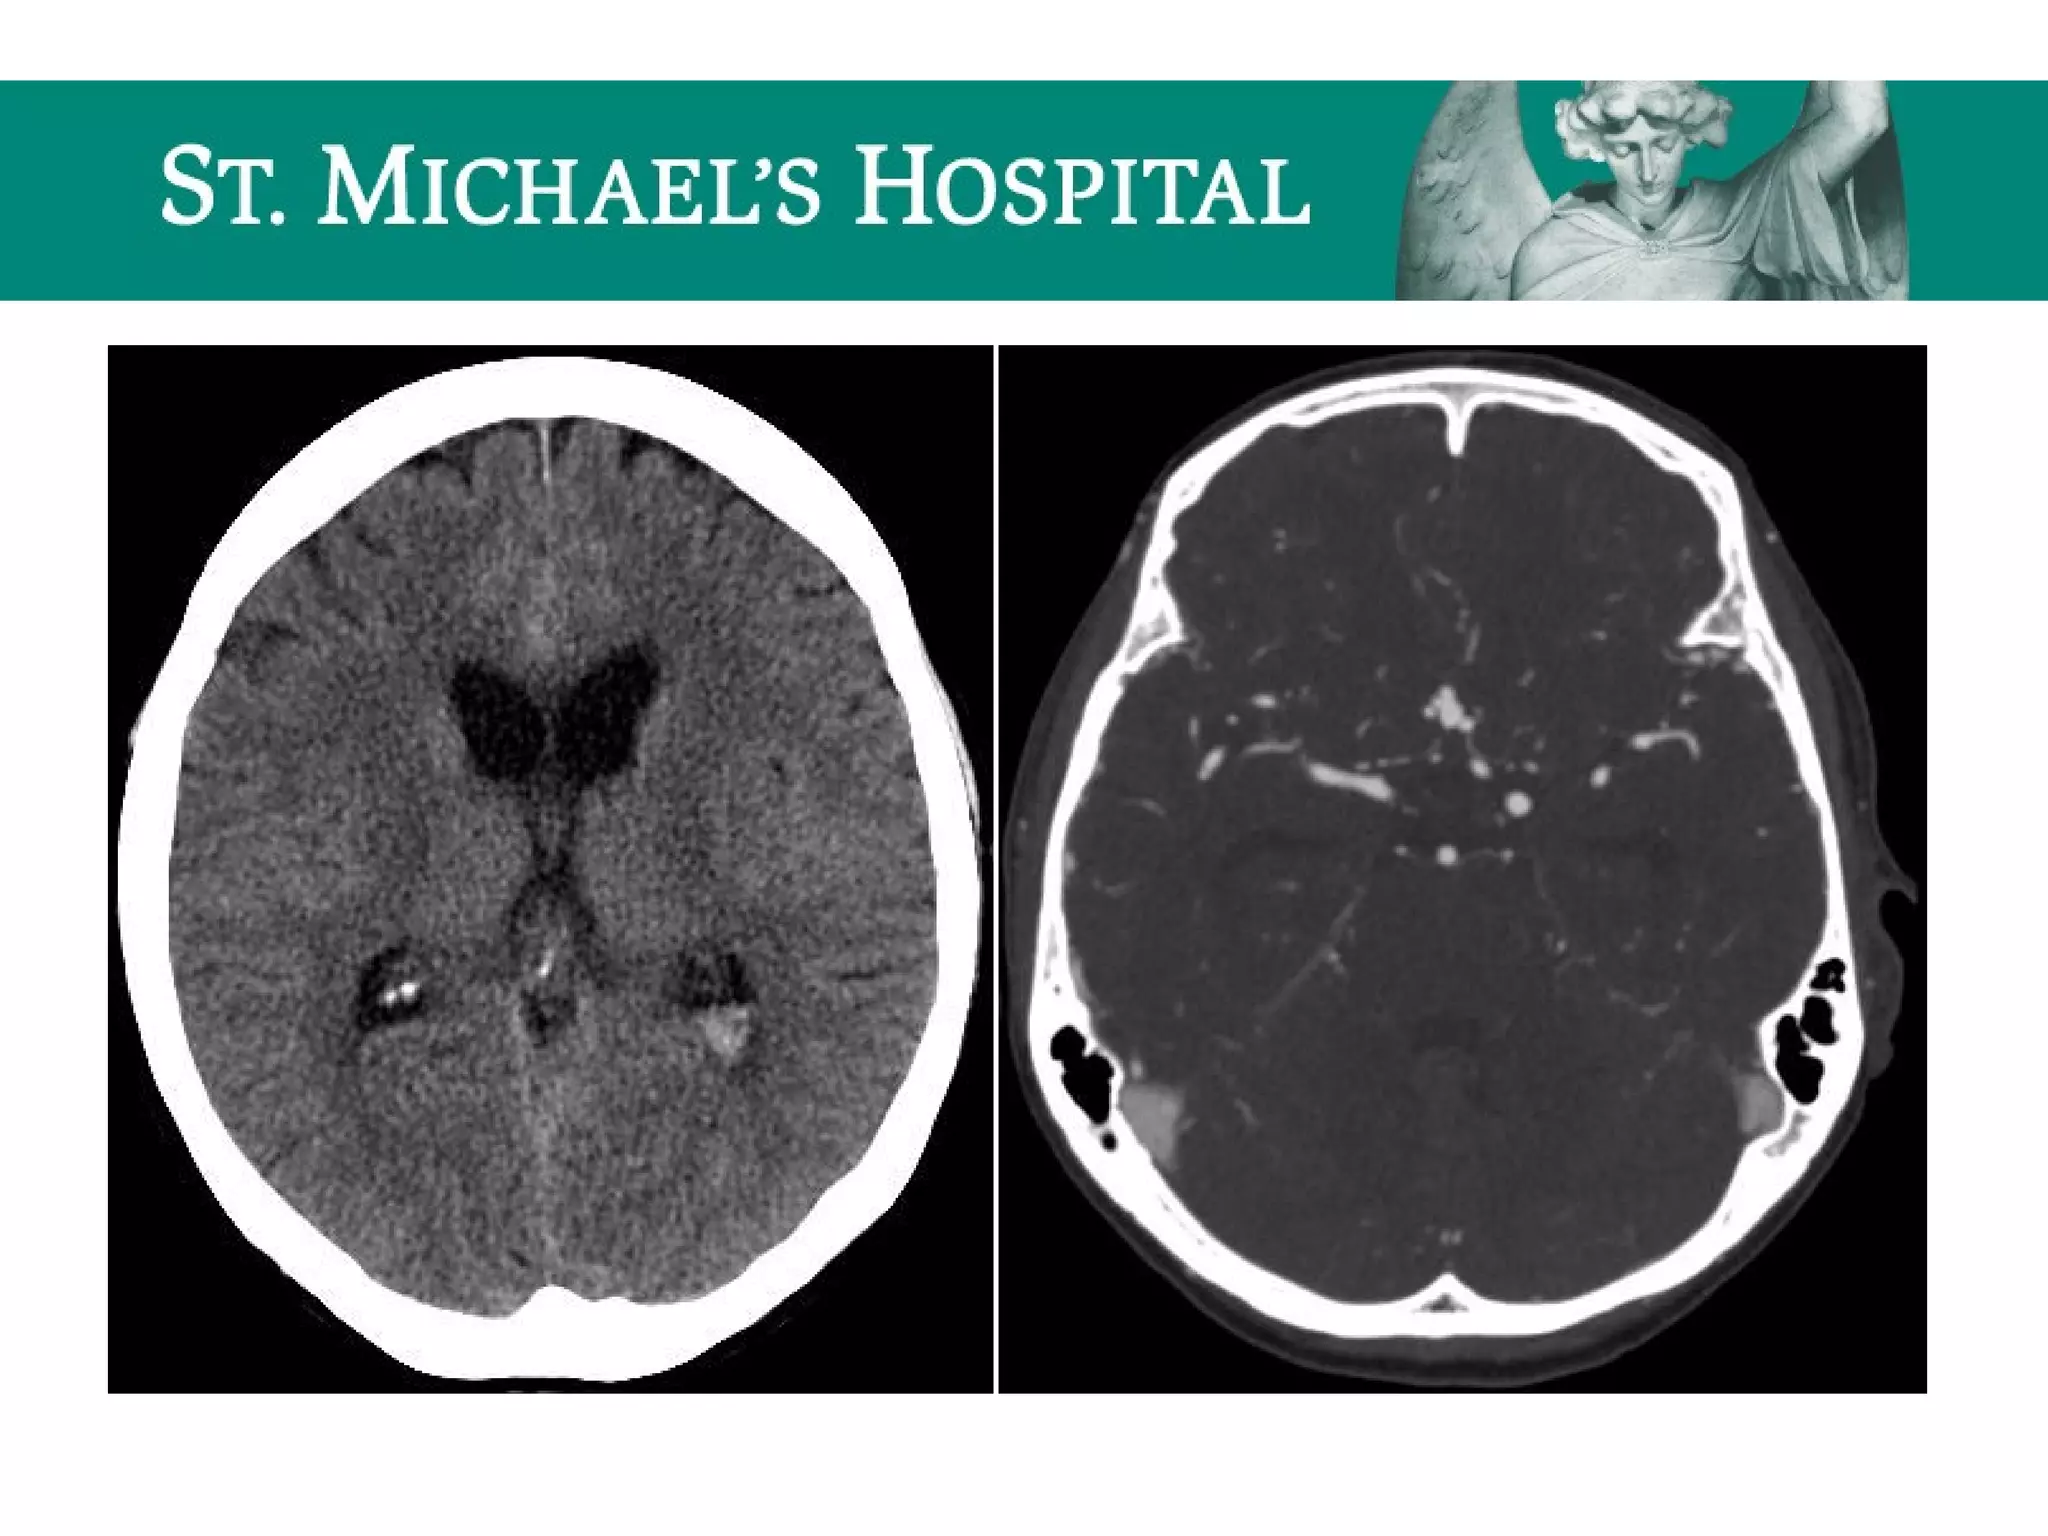

Unenhanced CT – Subdural Window

ONE MORE LOOK FOR EXTRA-AXIAL BLOOD!!!

SDH – CT Features

 Acute SDH

 high density fluid collection layering along the cerebral convexity

 crescentic (concave inner margin/convex outer margin)

 associated mass effect (sulcal effacement, ventricular compression, midline shift)

 Subacute SDH (1-2 weeks)

– “isodense” to grey matter

 Chronic SDH (> 2 weeks)

– “hypodense” to gray matter

– “acute-on-chronic”  hyperdense acute hemorrhage intermixed or layering dependently

within the chronic collection.